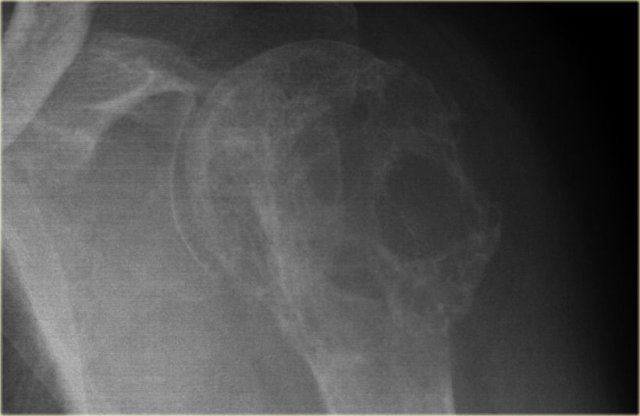

Solitary Bone Cyst

Solitary bone cyst, also known as unicameral bone cyst, is a true cyst.

Many well-defined osteolytic lesions are often called cystic, but this is a misnomer.

SBC frequently presents with a fracture.

Sometimes a fallen fragment is appreciated.

Predilection sites: proximal humerus and femur.

Usually less expansion compared with ABC.

Differential diagnosis: ABC, FD when cystic.

SBC may migrate from metaphysis to diaphysis during growth of the bone.

Discriminators:

- Must be under age 30.

- Must be centric